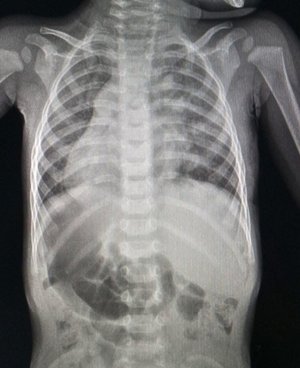

Львівські лікарі успішно прооперували пацієнта з надзвичайно рідкісною анатомічною особливістю — повною інверсією внутрішніх органів. У Дем’янчика серце та підшлункова залоза розташовані праворуч, а печінка ліворуч. Попри те, що таке «дзеркальне» розміщення зазвичай не заважає життю, у хлопчика виявили серйозну вроджену ваду серця.

Проблему помітили лише у 9 місяців під час планового огляду, коли педіатр почув шуми в серці. Обстеження показало дефект міжпередсердної перегородки: легеневі вени малюка впадали не в ліве передсердя, а в праве. Через аномальну анатомію ситуація була вкрай нестандартною, адже саме праве передсердя у Дем’янчика фізично знаходилося зліва.